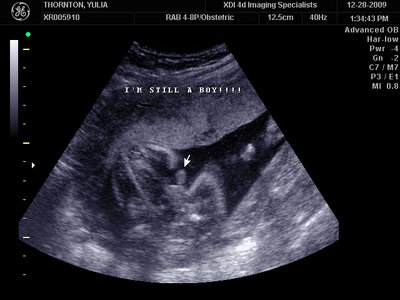

Ну ладно, тогда и я нашего писюна покажу  Надеюсь, Джеффри на меня не обидится Вот это в 23 недели: (там оборудование переключалось из режима 3Д в обычный 2Д)

| Вложения: |

MY BABY SONO!_2_15.JPG [ 112.35 КБ | Просмотров: 1085 ]

Sweetheart75 писал(а): Ну ладно, тогда и я нашего писюна покажу  Надеюсь, Джеффри на меня не обидится Вот это в 23 недели: (там оборудование переключалось из режима 3Д в обычный 2Д) Oоо, такое достоинство невозможно не заметить  А в 30 недель так вообще!